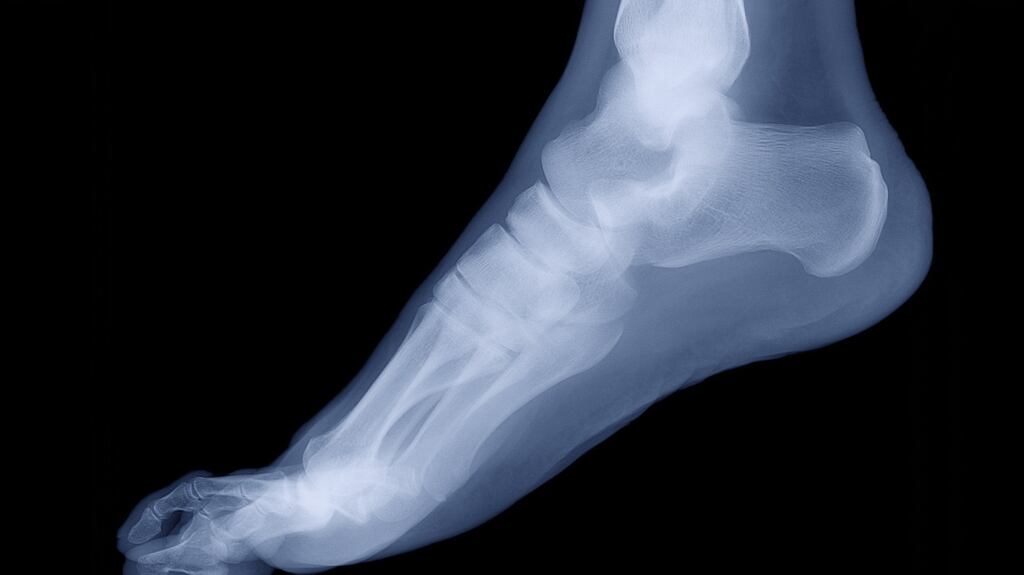

Barrister Breffni Gordon, counsel for Sophia, said following further complaints about being in pain while on a holiday in Bahrain, the girl’s father brought her for an X-ray which found she had a fractured fifth metatarsal.